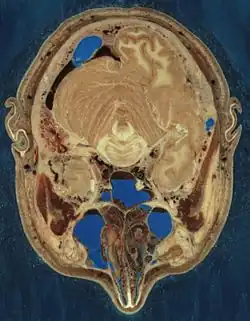

O Visible Human Project (Projeto Ser Humano Visível, em português) é um projeto proposto pela Biblioteca Nacional de Medicina dos EUA em 1986 para criar uma base de representações digitais da anatomia do corpo humano detalhada que sirva de referência para estudos anatômicos e para testar algoritmos de imagens médicas. Essas representações formam uma biblioteca de cortes anatômicos transversais, tomografias de raios X a fresco e congelado e de ressonância magnética. Desde 2019 as imagens do projeto podem ser acessadas livremente.

As imagens foram obtidas de um cadáver masculino (em 1994) e outro feminino (em 1995)[1]. Desde sua publicação, já foram utilizadas numa ampla variedade de projetos de uso educacionais, de diagnóstico, de realidade virtual, artístico, matemático e industrial.